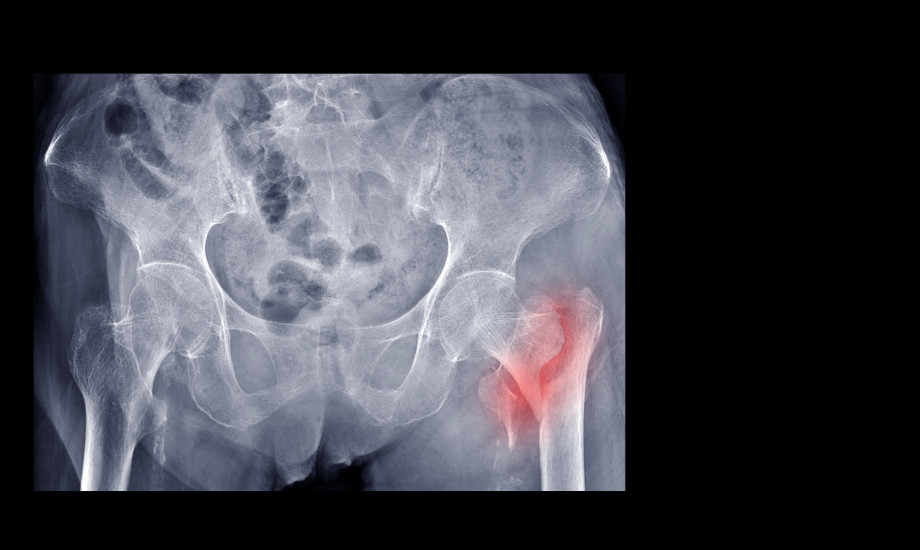

Wann treten Hüftfrakturen gehäuft auf?

Hüftfrakturen gehören zu den schwerwiegendsten Verletzungen im höheren Lebensalter. Eine neue Analyse aus England und Wales zeigte nun erstmals detailliert, welche Faktoren die Häufigkeit von Hüftfrakturen beeinflussen.